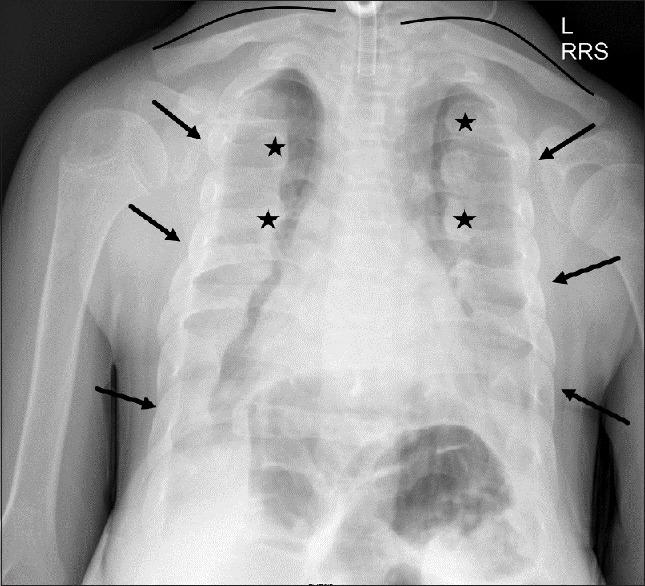

儿童间质性肺疾病:基于病例的影像学表现综述

Childhood interstitial lung disease: A case-based review of the imaging findings.

Childhood interstitial lung disease (chILD) consists of a large, heterogeneous group of individually rare disorders. chILD demonstrates major differences in disease etiology, natural history, and management when compared with the adult group. It occurs primarily secondary to an underlying developmental or genetic abnormality affecting the growth and maturity of the pediatric lung. They present with different clinical, radiologic, and pathologic features. In this pictorial review article, we will divide chILD into those more prevalent in infancy and those not specific to infancy. We will use a case based approach to discuss relevant imaging findings including modalities such as radiograph and computed tomography in a wide variety of pathologies.

摘要

儿童间质性肺疾病(chILD)由一大组种类繁多、各自罕见的疾病组成。与成人组相比,chILD在疾病病因、自然史和治疗方面存在重大差异。它主要继发于影响小儿肺部生长和成熟的潜在发育或基因异常。它们具有不同的临床、放射学和病理学特征。在这篇图片综述文章中,我们将把chILD分为在婴儿期更常见的疾病和并非婴儿期特有的疾病。我们将采用基于病例的方法来讨论相关的影像学表现,包括在各种病理情况下的X线片和计算机断层扫描等检查方式。